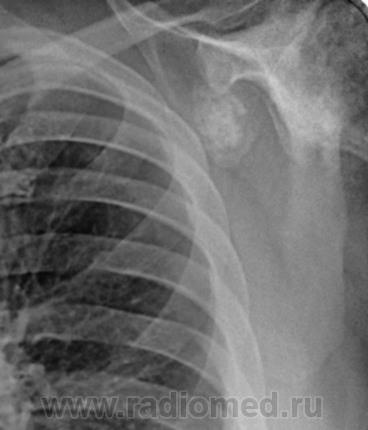

Пациент 60 лет, при прохождении проверочной флюорографии  обнаружены изменения со сторны плечевых суставов.Водитель троллейбуса.Страдает избыточной массой тела, люмбальгией, артороз коленных суставов.Непосредственно жалобы на плечевые суставы в медицинских документах не отражены. Какое будет мнение у коллег?

Пациент жалоб со сторны плечевых суставов не предъяляет и не помнит что бы когда- то что то беспокоило.Данных за сирингомиелию нет.

Александр, конечно надо доснять плечевые суставы... Из того, что есть: видимые отделы плечевых костей выглядят довольно симметрично, хотя слева и похуже, думаю - артроз. Весьма настораживает левая лопатка на предмет хондросаркомы

Снимки плечевых суставов.

Уважаемый Александр, приходиться признать, что на цифровой рентгенограмме легких изменения плечевых суставов видны лучше, чем на "обрезаных" и недоэкспонированых снимках суставов. По имеющимся данным могу только сказать, что деф. артроз с кистовидной перестройкой структуры есть. Под хрящевой опухолью (возможно - хондросаркома) левой лопатки я имела в виду тень, отмеченую красными стрелками, которая в поле снимка не вошла. Моя вина - в силу специфики работы такие узкоформатные снимки давно были вредными, т.к. очень часто патология остается за пределами снимка. Остается рекомендовать рентгенография левой лопатки в прямой передне-задней и косой проекциях, а лучше - КТ...